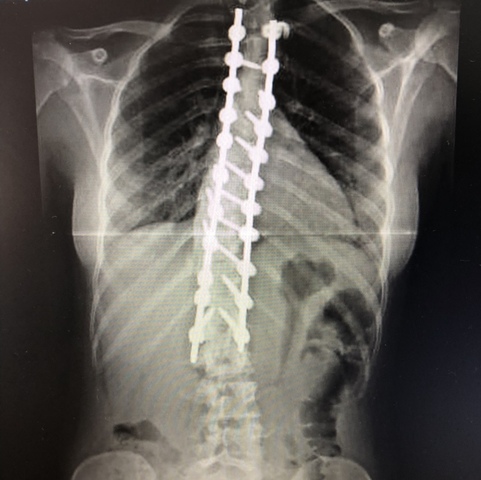

• Escoliosis

Escoliosis

Me detectaron escoliosis y estuve dos años con un corsét, finalmente me operé

• Mi operación

Mi operación

Me operé de la columna en Virgen del Rocío (Sevilla)